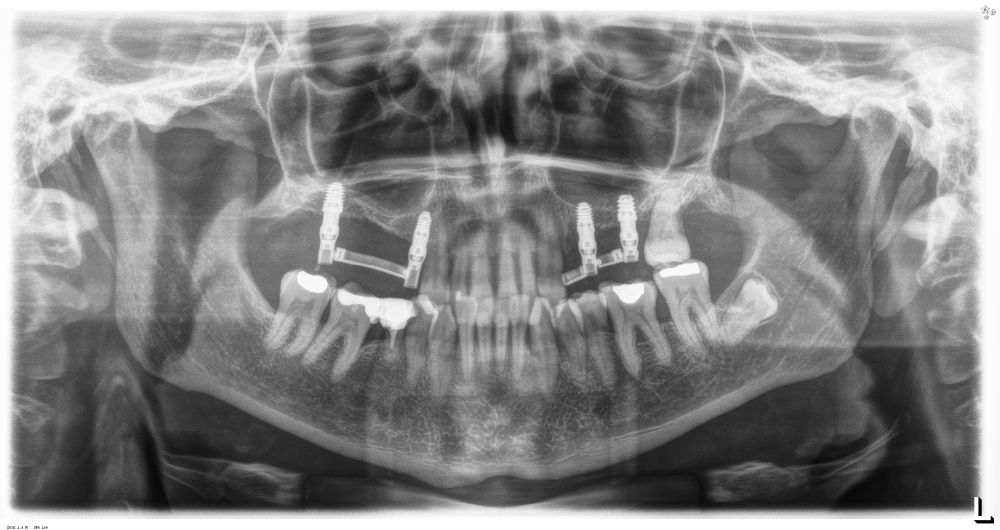

Como primer paso, se realiza un escaneado intraoral de la paciente, para poder generar un encerado virtual con las piezas que queremos rehabilitar con implantes (Figuras 6-8). Esto nos permite planificar con claridad el caso y desde el modelo tridimensional, generar los provisionales y las guías quirúrgicas basadas en la posición protésica, que desde el flujo digital pueden imprimirse (Figuras 9-14). Desde el encerado podemos además generar otras guías, en este caso radiológicas, con las que realizar el Cone-Beam Computed Tomography (CBCT) de planificación. Con esta información tenemos en el mismo estudio radiológico la fusión de nuestra planificación quirúrgica y la posición real de la prótesis adaptada a la oclusión, muy útil para generar una planificación que contempla todos los parámetros. En este caso, se planifican implantes cortos de 6,5 mm en el primer cuadrante, de morfología Core-Xâ, para lograr una correcta estabilidad primaria en un tipo óseo IV como vemos en el corte seccional (Figuras 15 y 16). En el segundo cuadrante, con similares características, planificamos implantes de 6,5 y 5,5 mm de longitud (Figuras 17 y 18).

Una vez colocados los implantes, podemos realizar incluso carga inmediata, ya que, aun en condiciones de baja densidad y escasa altura ósea residual, con el protocolo anteriormente descrito se logra la estabilidad primaria suficiente (Figuras 25 y 26). Elaboramos una prótesis de carga inmediata atornillada sobre transepitelial (colocados en el momento de la cirugía y mantenidos posteriormente para no romper el hermetismo), confeccionada en resina con una estructura de barras articuladas. Esta prótesis nos proporciona carga progresiva mientras se produce la integración de los implantes, lo que favorece este proceso y permite reconstruir el patrón oclusal perdido, dado que presenta múltiples ausencias dentales del sector posterior maxilar. La carga progresiva en los implantes dentales es una técnica que permite una transición gradual de fuerzas sobre el implante, favoreciendo la adaptación biológica y la estabilidad ósea a lo largo del tiempo. En lugar de aplicar una carga inmediata completa, se introduce una presión controlada y creciente durante el periodo de cicatrización, lo que facilita una mejor osteointegración y reduce el riesgo de sobrecarga temprana. Este enfoque es especialmente útil en casos donde la calidad ósea es comprometida o cuando se busca una mayor predictibilidad en el tratamiento12.

Transcurridos 6 meses desde la carga inicial progresiva, se puede elaborar la prótesis definitiva, trasladando los parámetros de la prótesis provisional (Figura 27). La paciente continúa en seguimiento durante un año, realizándose radiografías de control para el monitoreo del hueso crestal, sin encontrarse pérdida ósea asociada en ninguno de los implantes (Figuras 28-29).